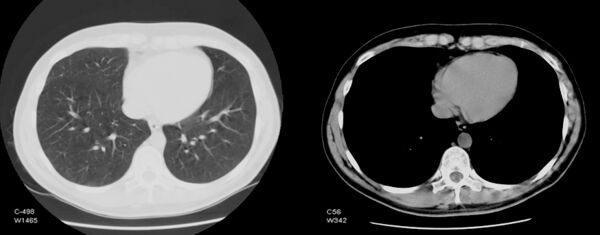

Обычный компьютерный монитор способен отображать до 256 оттенков серого цвета, некоторые специализированные медицинские аппараты способны показывать до 1024 оттенков. В связи со значительной шириной шкалы Хаунсфилда и неспособностью существующих мониторов отразить весь её диапазон в чёрно-белом спектре, используется программный перерасчёт серого градиента в зависимости от интересуемого интервала шкалы. Чёрно-белый спектр изображения можно применять как в широком диапазоне («окне») денситометрических показателей (визуализируются структуры всех плотностей, однако невозможно различить структуры, близкие по плотности), так и в более-менее узком с заданным уровнем его центра и ширины («лёгочное окно», «мягкотканное окно» и т. д.; в этом случае теряется информация о структурах, плотность которых выходит за пределы диапазона, однако хорошо различимы структуры, близкие по плотности). Изменение центра окна и его ширины можно сравнить с изменением яркости и контрастности изображения соответственно.

- Подозрение на повреждение лёгких по типу «матового стекла» в результате пневмонии, сопровождающей такие коронавирусные ОРВИ как COVID-19